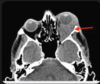

Red flags for orbital cellulitis?

A

• systemic features of inffection

• concurrent sinusitis

• abnormal visual acuity or RAPD

sinusitis can be the source of infection

infection can spread to carvenous sinus causing throbosis, meningits, abscess, frank sepsis